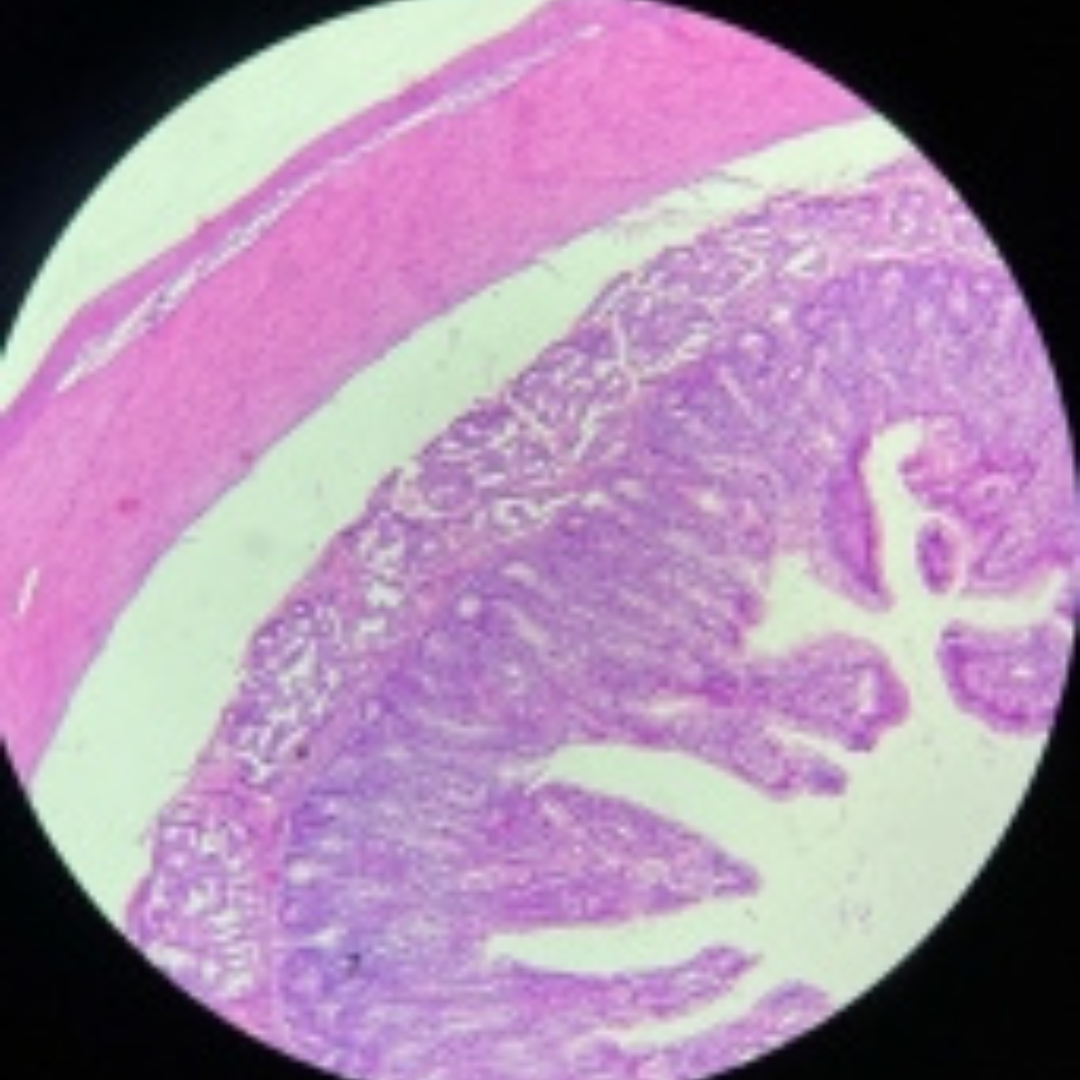

Jejunum

Duodenum

Jejunum

Jejunum

Jejunum

Jejunum

Jejunum

Jejunum